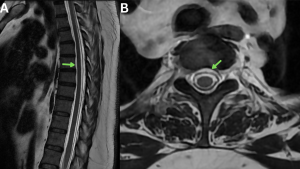

Fig 12: Clinical History: A 29-year-old man presenting with a sudden-onset postural headache.

Figures A and B. Sagittal and axial T2-weighted MR images demonstrating a long-segment T2 hyperintense anterior spinal epidural fluid collection (green arrows).